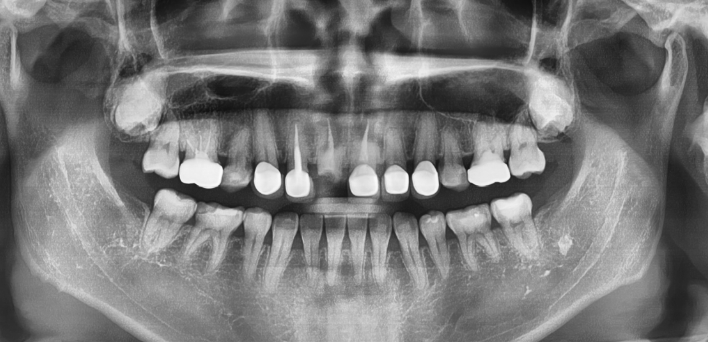

임플란트 : 손 ** 님 (50대)

Before Before

2020.02.30

After After

※ 더서울치과의원은 의료법을 준수하며 위 케이스는 실제 환자의 동의를 얻은 사례로 치료 전, 후가 동일한 환경에서 촬영되었습니다.

환자 케이스에 따라 부작용이 발생할 수 있습니다. 이 부분은 의료진의 충분한 상담과 체크를 통해 예방하고 줄일 수 있습니다.

[임플란트 부작용] 수술 후 관리가 소홀할 경우 출혈, 주위염 등의 부작용이 발생할 수 있어 구강 위생을 철저히 유지하고, 정기적인 검진을 통해 상태를 점검하는 것이 중요합니다.

환자 특징

환자 특징01무치악 상태

환자 특징02수년간 무치악으로 지내심

임플란트가 불가능할것이라

생각하고 내원

위, 아래 6개씩 식립

디지털 풀아치 임플란트